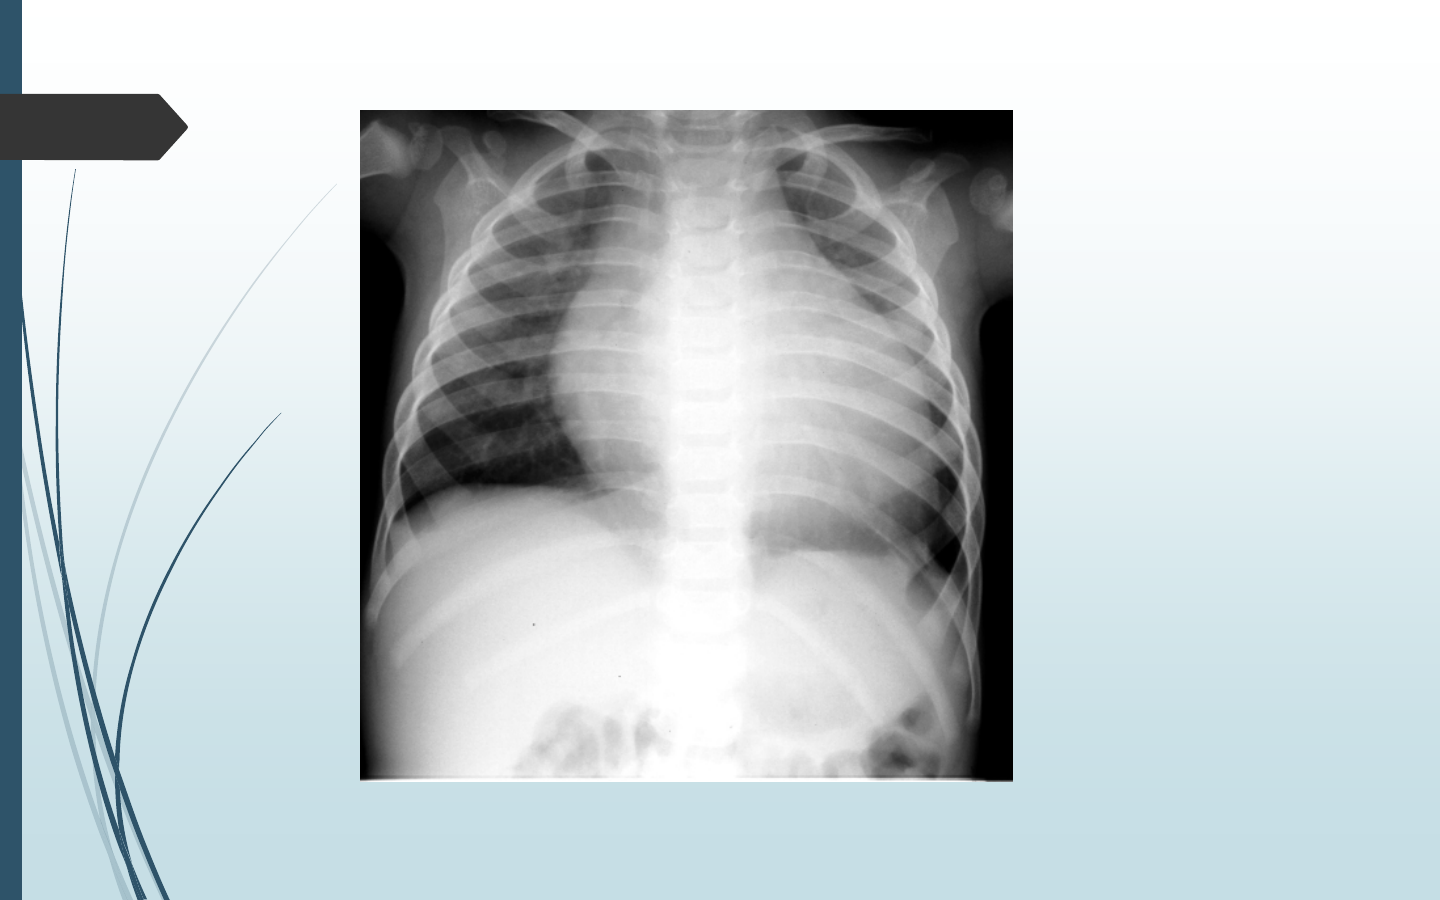

I Infection (otite, pneumopathie, méningite, pyélonéphrite)